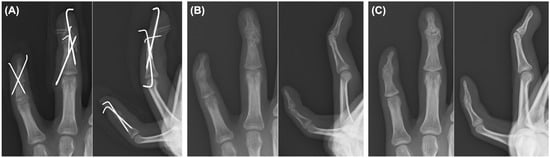

Background and Clinical Significance: Mallet finger is a common injury of the extensor mechanism at the distal interphalangeal (DIP) joint; however, open double mallet lesions are rare and may present a complex reconstruction challenge. Case Presentation: A 15-year-old male high school student who sustained an open injury to the left ring and little fingers after a high-energy buggy accident. The ring finger showed an open double mallet lesion in which the extensor tendon remained attached to a tiny avulsion fragment, and a separate dorsal base fragment was also present. The adjacent little finger had a concomitant open fracture with substantial soft tissue injury. Emergency surgery was performed on the day of the injury. For the ring finger, reduction of the tendon-attached avulsion fragment and separate dorsal base fragment was achieved using extension-block pinning, transarticular DIP pinning, and pull-out fixation over a volar button. For the little finger, cross-pinning was performed because the distal fragment was too small for stable non-transarticular fixation. Serial radiographs showed maintained alignment and progressive healing. At the final follow-up, 21 months after the injury, residual deformity and limitation of DIP motion remained; however, no infection, major skin complications, or nail deformity were observed. The little finger DIP joint became ankylosed, whereas some residual mobility remained in the ring finger DIP joint. Despite persistent functional limitations, the patient was able to continue school attendance and percussion-related activities. Conclusions: This case highlights that in an open double mallet lesion, disruption of both the tendon-attached fragment and its bony bed should be considered, and stabilization of the base may be useful in selected injury patterns before definitive tendon-side repair. Full article